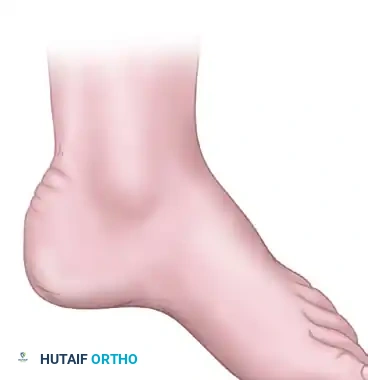

Lateral and frontal view of a plantar flexed first ray as seen in Charcot-Marie-Tooth disease compared with a normal foot.

When the plantar flexed first ray strikes the ground, the heel is forced into varus.

Normal calcaneal pitch, but forefoot equinus in a patient with Charcot-Marie-Tooth disease. The calcaneal pitch angle measures the degree of calcaneus deformity.